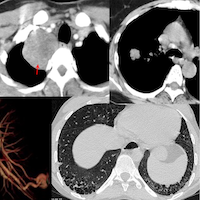

A recent lecture I gave on interstitial lung abnormality (ILA), which is an update to the snippet that I did in July 2025 when the new guidelines came out.

Interstitial lung abnormality (ILA) is becoming an important subject because of a variety of issues, including the increased all cause mortality and progression to ILD. It is important to understand the current status of ILA imaging.

The lecture focusses on

- Current guidelines

- New information since the guidelines on histopathology and FANO